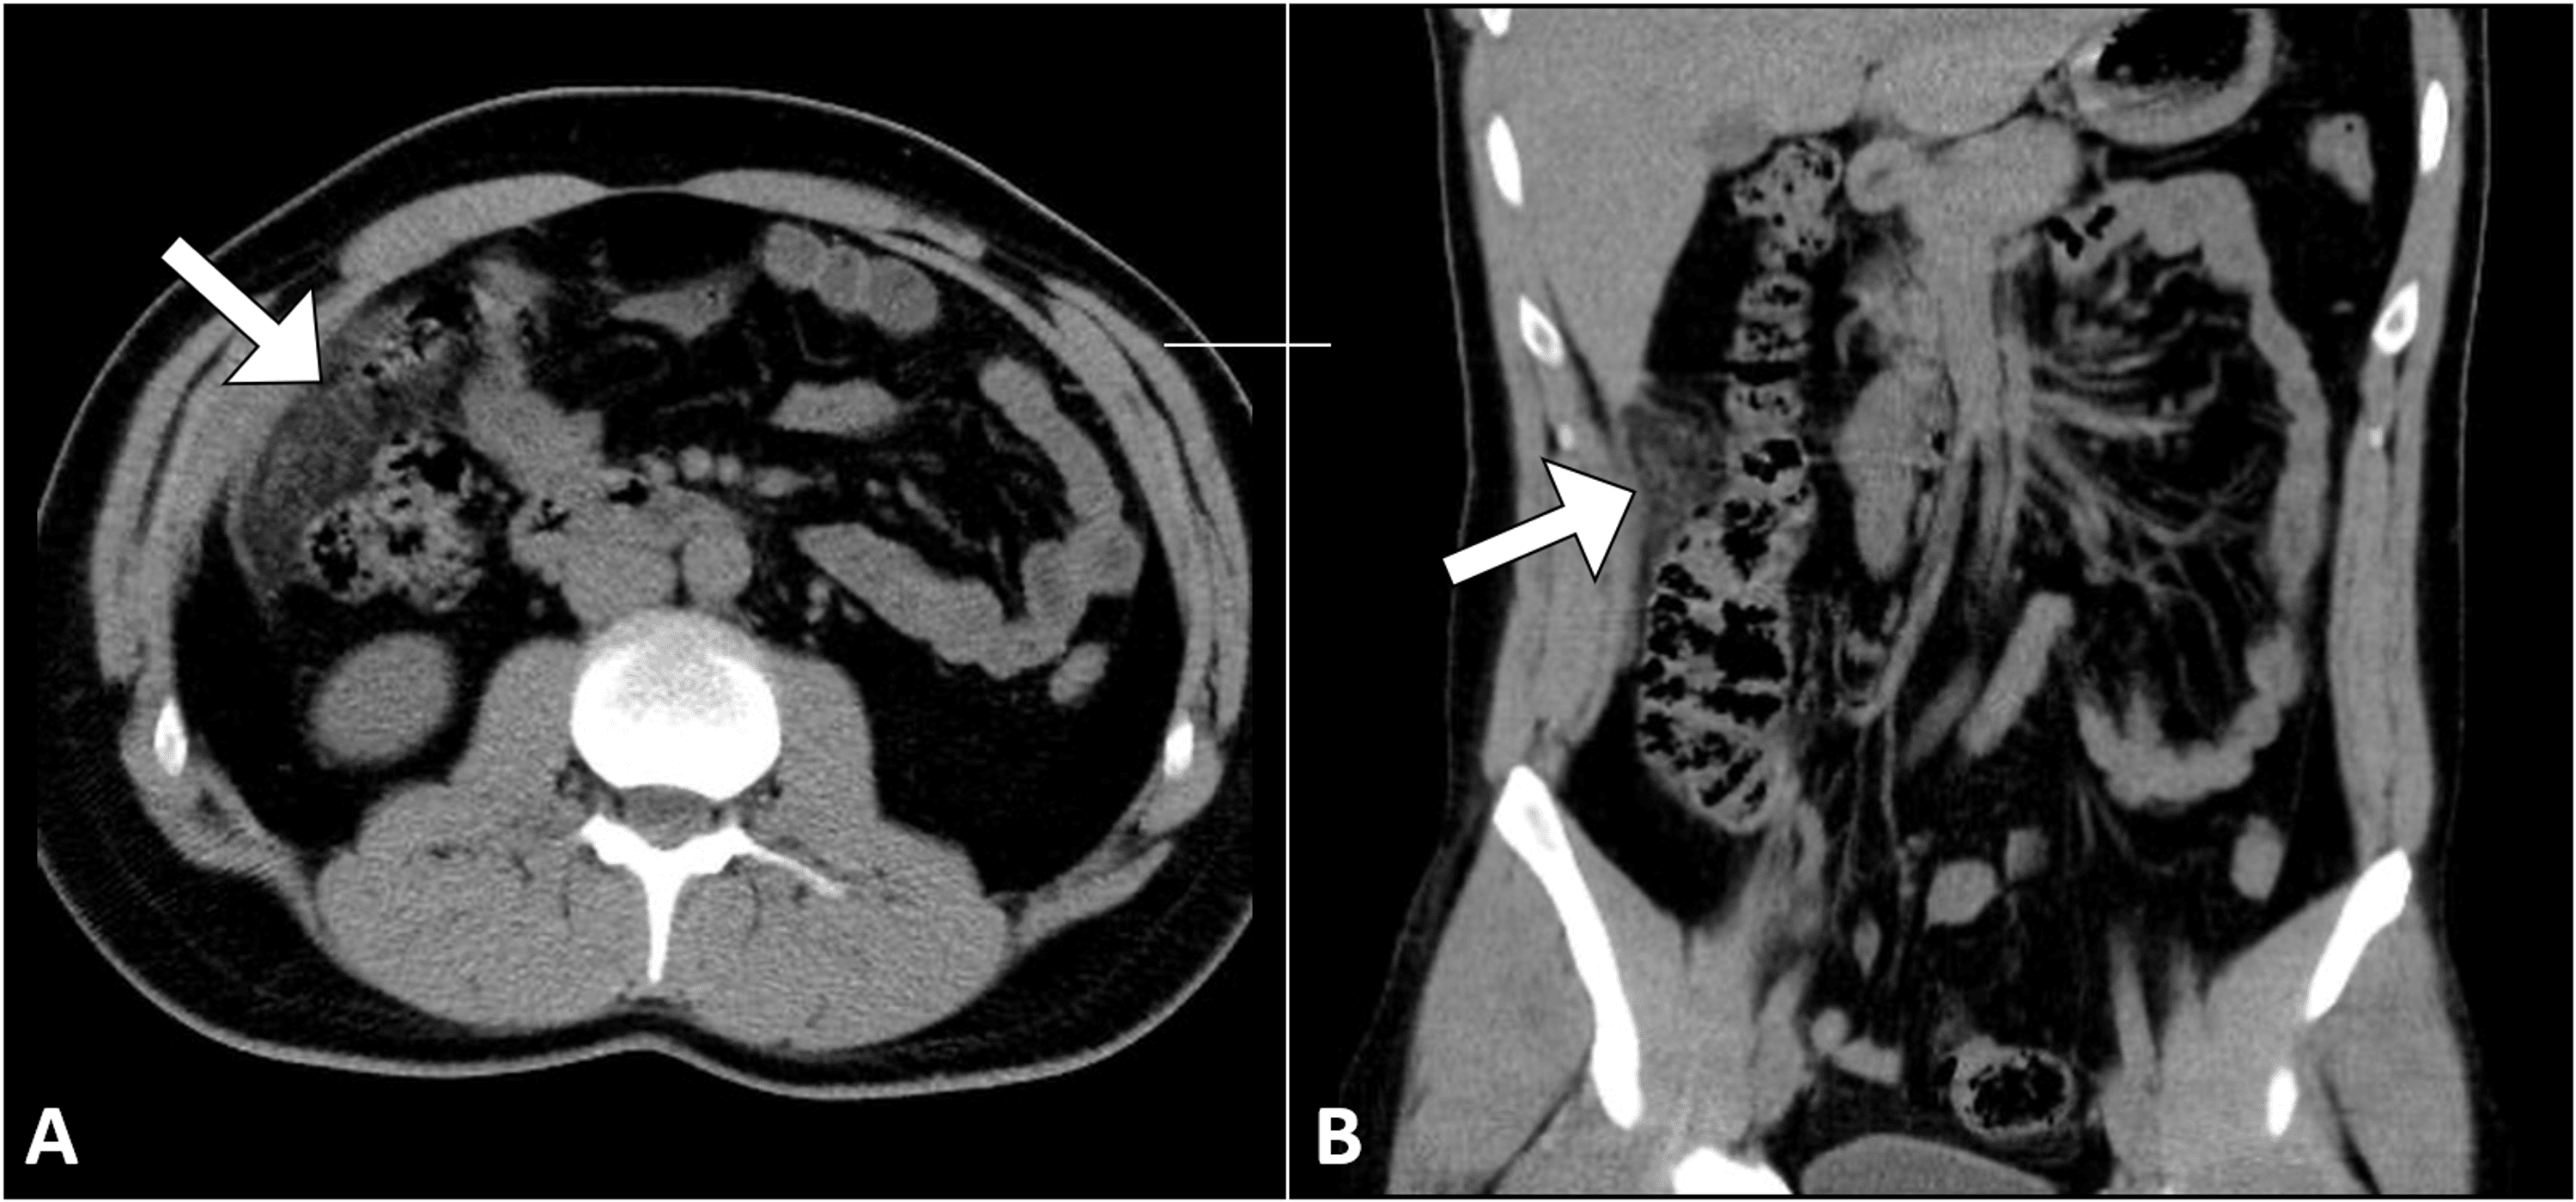

From radiologycases.my

Omental cake from metastatic lung carcinoma Radiology Cases Omental Adhesion Disease Omentum cancer starts in the fatty tissue (omentum) that drapes over all the organs in your abdomen. Learn about abdominal adhesions causes (pelvic inflammatory disease, previous surgeries), symptoms (abdominal pain or cramping), and. Scars on the inside after surgery are known as abdominal adhesions. Here are five things to know about this scar tissue. Abdominal adhesions are bands of scar. Omental Adhesion Disease.

Omental cake from metastatic lung carcinoma Radiology Cases Omental Adhesion Disease Omentum cancer starts in the fatty tissue (omentum) that drapes over all the organs in your abdomen. Abdominal adhesions are bands of fibrous scar tissue that form on organs in the abdomen. It’s extremely rare to have a tumor. They can cause organs to stick to. Abdominal surgery is the most common. Here are five things to know about this. Omental Adhesion Disease.